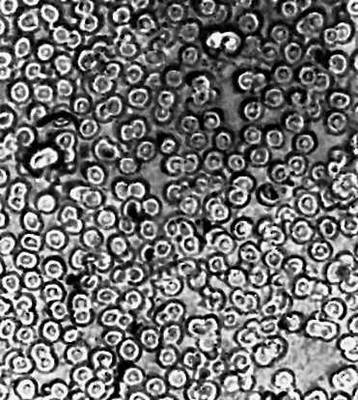

Большая Советская Энциклопедия (УЛ) - i010-001-245861840.jpg

Рис. 5а. Красные кровяные тельца, полученные оптическим микроскопом.